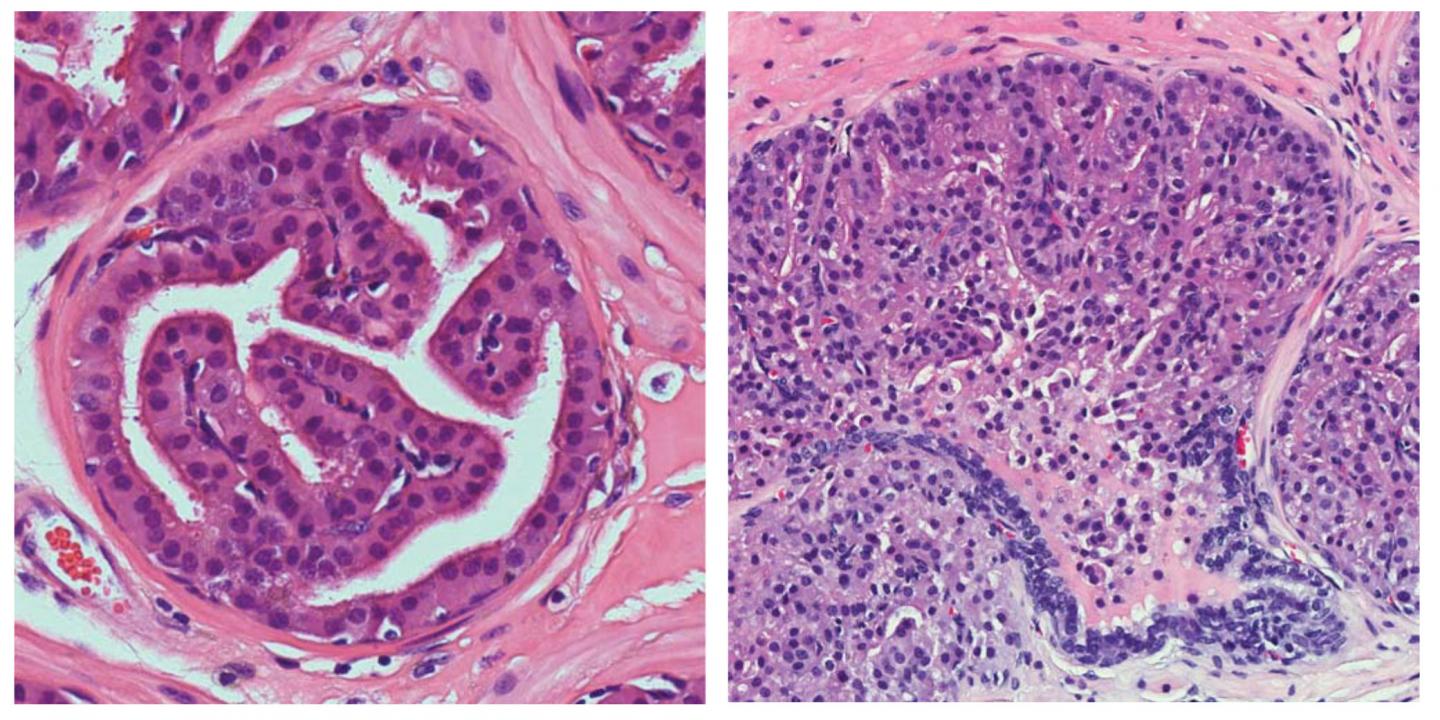

Mice lacking Importin-11 showed lower levels of PTEN protein and developed lung adenocarcinomas and prostate neoplasias. Mutations in the gene encoding Importin-11 have been identified in human cancers, and Trotman and colleagues found that tumors from lung cancer patients lacking Importin-11 tended to show low PTEN levels as well. The researchers estimate that loss of Importin-11 may account for the loss of PTEN in approximately one third of lung cancer patients lacking this key anti-cancer protein.